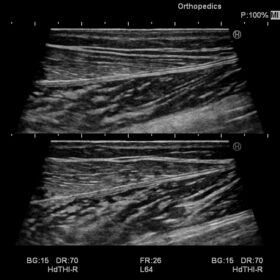

Ultrasound Noblus – Image Gallery and Videos

Radiology 2D, Color, PW and Elasto mode

Using Hitachi’s own broadband technology to increase the harmonic frequency bandwidth, the High definition dynamic Tissue Harmonic Imaging (HdTHI) mode gives you both high resolution and excellent penetration. The HI Rez+ tissue adaptive filter optimises contrast resolution, border enhancement and noise suppression without reducing frame rate, and the HI Com, real-time spatial compounding technology, that uses multiple beams on transmit and receive, is especially beneficial for clarifying luminal structures